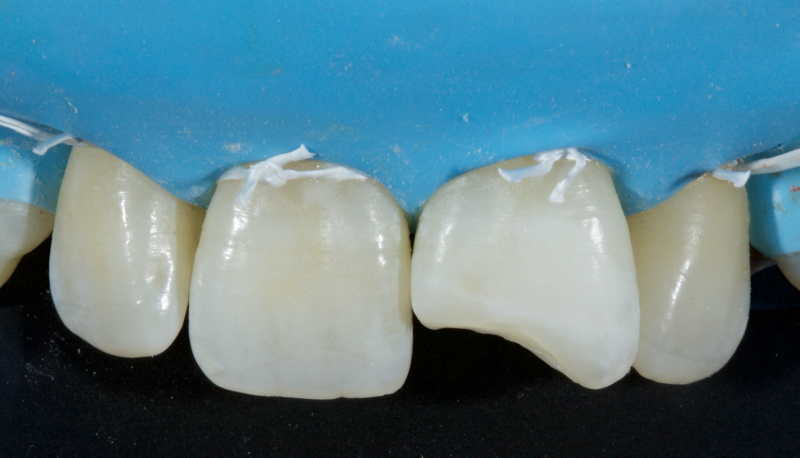

In this example of the Modified Walking Bleach Approach, the patient presented with a discolored upper right central incisor (1.1, Fig. 7). The old restoration was removed, an endodontic retreatment was carried out, and a coronal barrier seal was placed (Fig. 8). The access cavity was left open (Fig. 9).

The patient carried out the modified walking bleach technique with a nightguard for 48 hours (Fig. 10). I prefer to mark the night guard with a Sharpie marker to enable the patient to visualize the correct tooth to treat. The patient returned for review after successful whitening (Fig. 11).